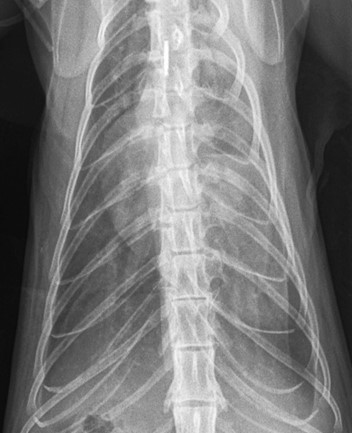

Radiography

Radiographing dyspnoeic cats is best avoided due to the obvious stress involved in restraint. If this is your only option, then placing the cat in sternal recumbency with no restraint, or in a cat carrier surrounded by foam pads is the safest technique.

Radiographs from dyspnoeic cats can be very difficult to interpret, but findings associated with congestive heart failure in cats include:

- Left atrial enlargement – a “kidney bean” shape on the lateral view or “valentine” shape on the DV (note this is not always particularly obvious, and many cats do not have generalised cardiomegaly).

- Congestion of pulmonary lobar vessels – often most prominent on the DV view. These are unlikely to be even visible in cats with other causes of a visible lung pattern

- Patchy interstitial/alveolar lung pattern associated with pulmonary oedema – often spreading from the region of the pulmonary vessels but can be very variable in cats.